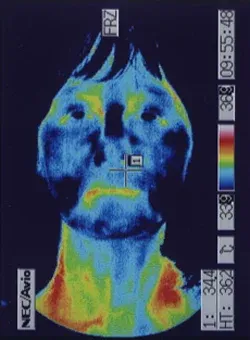

突発性難聴の治療で高圧酸素室に入って治療をした時、耳ぬきがうまくいかずに滲出性中耳炎になってしまいました。痛みは無いので鼓膜に穴をあけるのもとても不安です。滲出性中耳炎は、鍼治療でよくなりますか?

内耳のリンパの流れを良くすることで改善することが多いです。

滲出性中耳炎は、痛みが無いので癖になってしまうことが多いのですが、比較的、鍼治療が効果的です。お医者様は、鼓膜にチューブを入れることがあるのですが、鼓膜の中に落ち込んでしまうこともあるので、鍼治療をされる方も多いです。不安や恐怖が多いほど、症状が改善しなくなることが多いので、ストレスをためないようにしましょう。

詳しくは、 滲出性中耳炎の鍼治療 をご覧ください。